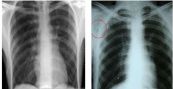

Chụp X-quang là chụp ảnh phóng xạ thường được thực hiện nhất. Chụp X-quang thường trong thủ tục đầu tiên mà sẽ trải qua nếu bác sĩ nghi ngờ có bệnh tim hoặc phổi. Để hiểu rõ hơn về phương pháp này, mời các bạn cùng tham khảo bài viết dưới đây.